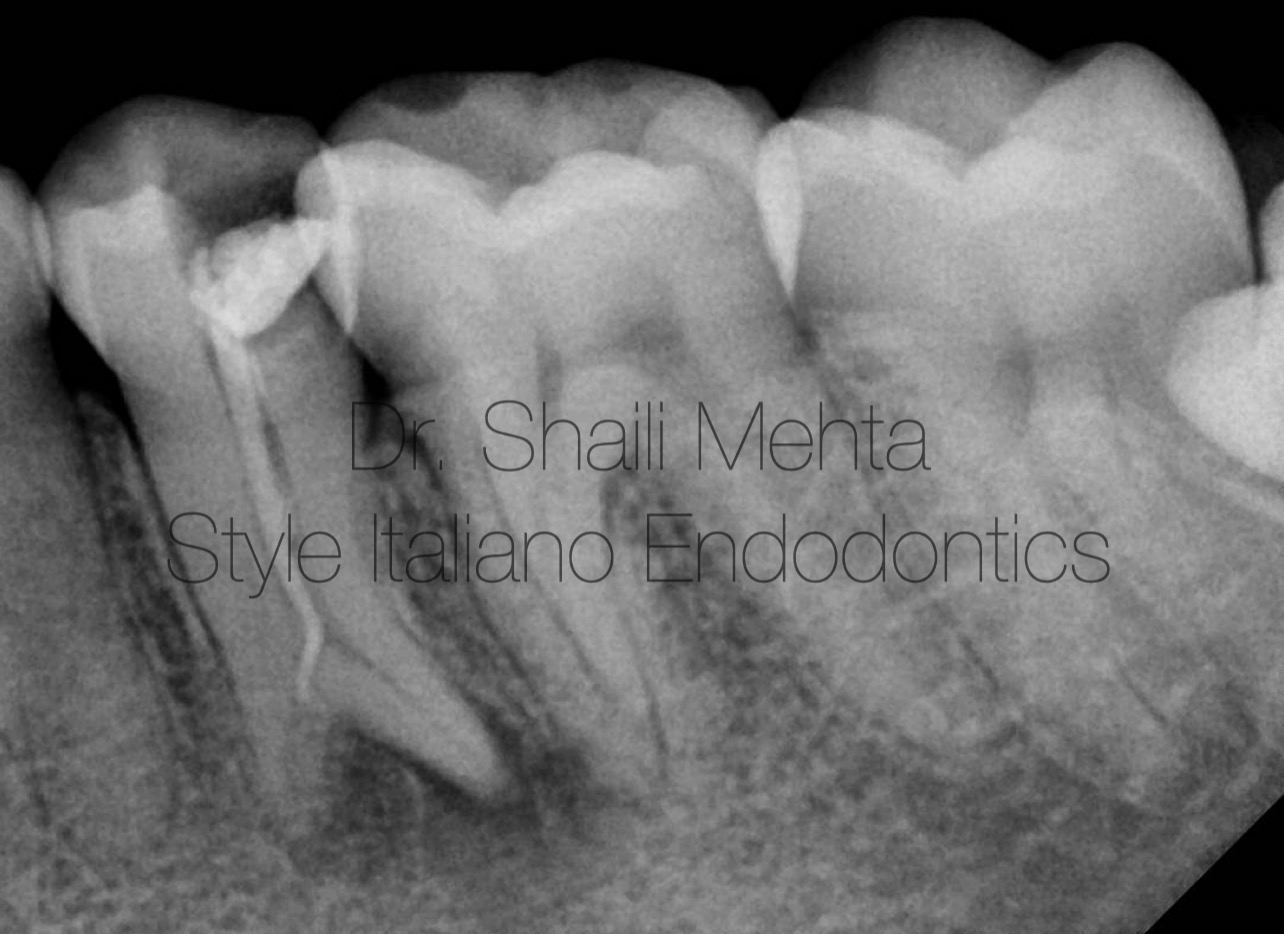

Fig. 2

Under adequate local anesthesia and strict rubber dam isolation, the existing restoration and coronal gutta-percha were removed. The access cavity was refined, and initial exploration under the DOM confirmed only one centrally positioned, previously treated orifice. The pulp chamber floor was systematically explored by troughing the lingual developmental groove using hand files (Mani,Inc). This crucial step successfully localized a distinct, separate, and untreated lingual canal orifice, confirming a true Vertucci Type IV bifurcation originating high in the middle third of the root.

Working lengths were confirmed radiographically at 21.5 mm for both the buccal and lingual canals. (Figure 2). Figure 2: Working length radiograph confirming the Vertucci Type IV bifurcation with two separate canal diverging apically